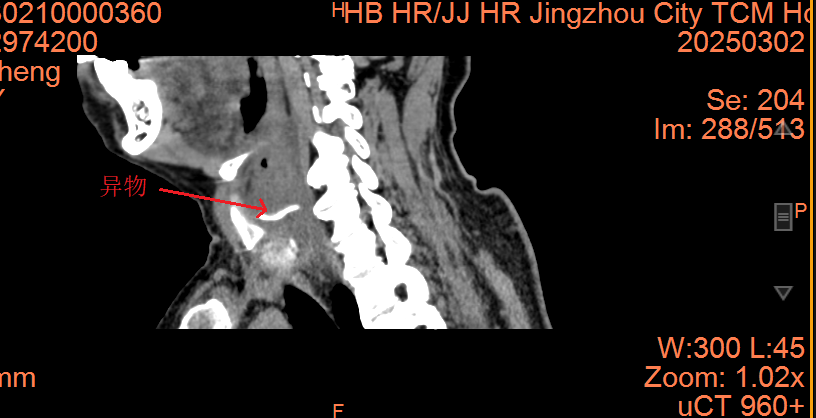

這名73歲的男性患者因誤食魚刺導(dǎo)致咽痛、吞咽困難和聲音嘶啞長達(dá)三天,并在外院接受抗炎治療后未見好轉(zhuǎn),隨后緊急轉(zhuǎn)入荊州市中醫(yī)醫(yī)院。入院檢查發(fā)現(xiàn),魚刺呈“S”形嵌頓于右側(cè)聲門旁間隙,長度約3cm,周圍組織嚴(yán)重水腫。此外,患者電子喉鏡提示急性會(huì)厭炎及聲帶麻痹,隨時(shí)可能引發(fā)窒息或致命性感染。

面對(duì)高齡、基礎(chǔ)疾?。ǜ哐獕海┘皬?fù)雜解剖粘連等風(fēng)險(xiǎn),耳鼻咽喉頭頸外科主任劉燕青帶領(lǐng)的團(tuán)隊(duì)迅速制定了詳細(xì)的手術(shù)方案。先行食管鏡探查定位異物,發(fā)現(xiàn)梨狀窩黏膜破損,異物被炎性組織緊密包裹,無法以內(nèi)鏡方式安全取出。團(tuán)隊(duì)果斷轉(zhuǎn)為頸側(cè)入路切開取刺,沿右頸作3.5cm切口,逐層分離頸闊肌、帶狀肌,切除部分甲狀軟骨板,暴露聲門旁間隙,術(shù)中見魚刺穿透黏膜,團(tuán)隊(duì)采用“鈍性剝離+分段剪斷”策略,分三段取出長約3cm的魚刺,并進(jìn)行了穿孔黏膜的縫合修復(fù)。術(shù)后,患者接受了包括抗感染、抗炎、護(hù)胃、霧化、降壓、營養(yǎng)支持及中醫(yī)康復(fù)在內(nèi)的綜合治療。復(fù)查時(shí),食管鋇餐造影未見造影劑滲漏,患者康復(fù)情況良好,已康復(fù)出院。